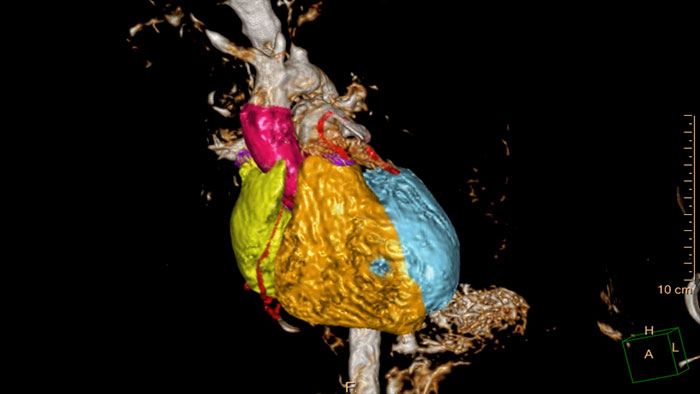

CT cardiac analysis

This application is based on an automatic 3D model-based whole-heart segmentation and zero-click coronary artery segmentation. This enables automatic extraction and visualization of the entire coronary tree.

Benefits